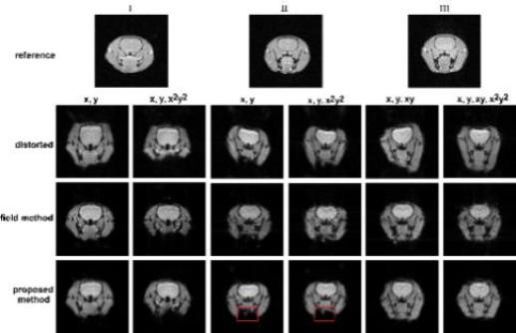

我们在深度学习与超快速磁共振成像方面的结合进行了深度研究,并取得许多重要成像。我们研究了基于深度学习的超快速多参数磁共振成像重建,并取得良好的效果,如图1所示。我们还研究了利用深度学习对磁共振成像进行无参考扫描的扭曲校正,如图2所示。

图2.利用深度学习进行的无参考扫描扭曲校正算法